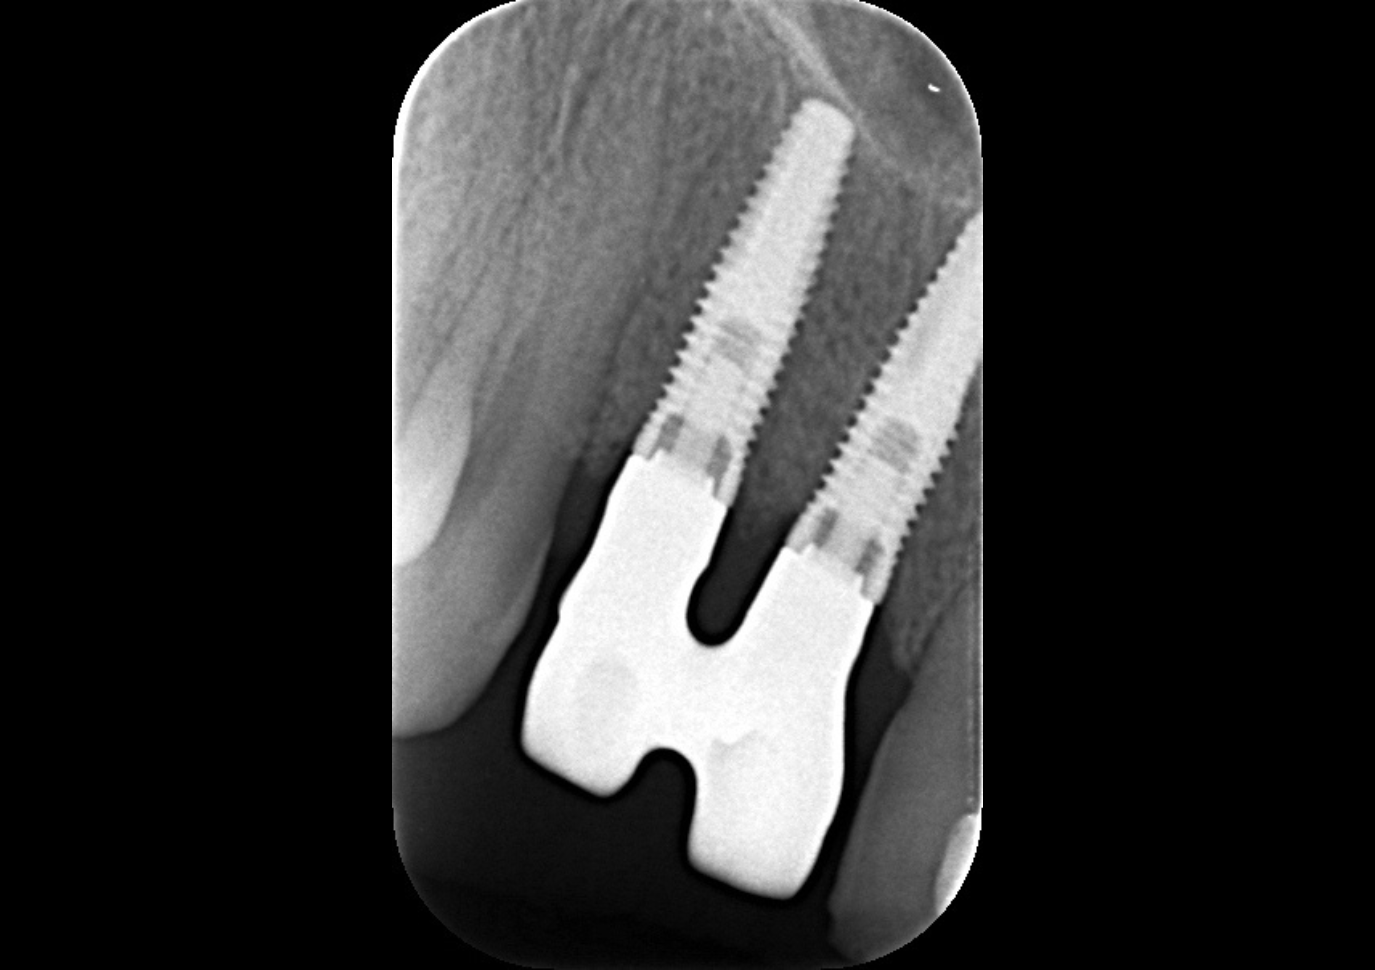

Figure 4.

Radiographic image showing stable bone levels.